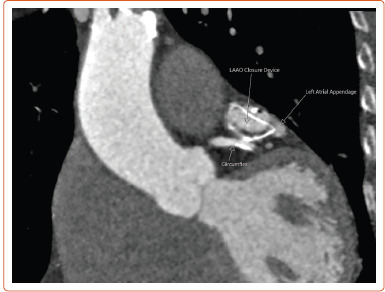

An 80-year-old patient presented with a rare complication: a late coronary-cameral fistula following implantation of an Amulet (Abbott) left atrial appendage occlusion device. Microperforations from the device's anchoring tines have previously been suggested as a possible mechanism of fistula formation, a complication reported in two other cases. We propose an alternative theory of potential collateralisation of the threatened appendage from the nearby circumflex artery.